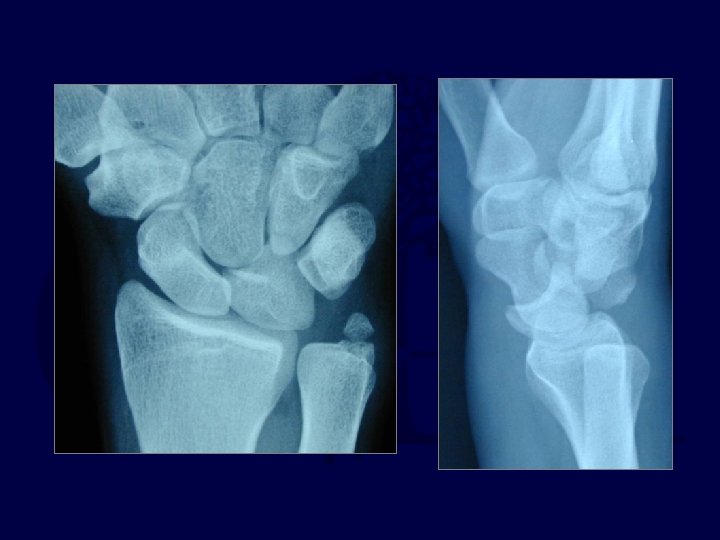

Imaging • Note lack of “colinearity” among the radius, lunate, and capitate on the lateral x-ray.

Imaging • Note loss of normal carpal “arcs” and abnormal widening of the scapholunate interval. • Look for associated fractures “trans-scaphoid” injuries

X-ray usually Obvious

X-ray may be subtle